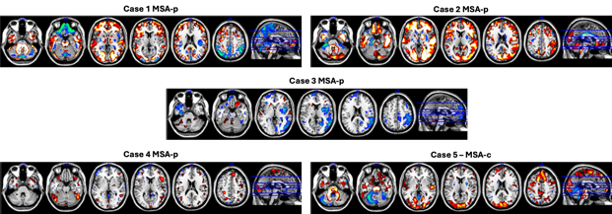

Results: Single-subject W-maps revealed significant variability in cholinergic system status across the 5 MSA cases. Two MSA-parkinsonian (MSA-p) patients (Case 1 and Case 2, Figure 1) showed widespread cortical upregulation in the frontal (esp. orbitofrontal regions) and parietal cortices, with shared posterior putamen downregulation. Case 1 had more extensive cortical downregulation, lower Montreal Cognitive Assessment (MoCA) (23 vs. 25), and was younger (69 vs. 75). Case 3 (MSA-p) showed right-lateralized fronto-parietal downregulation, minimal upregulation, the highest fall frequency (1/day), but intact cognition (MoCA 30). Case 4 (MSA-p) had limited frontal downregulation but extensive upregulation in frontal, sensorimotor, and cerebellar regions, corresponding to low Postural Instability and Gait Disorder scores (7), no falls, and MoCA 24. The only MSA-cerebellar case had localized cerebellar downregulation and upregulation in the posterior and prefrontal cortices.

Figure 1